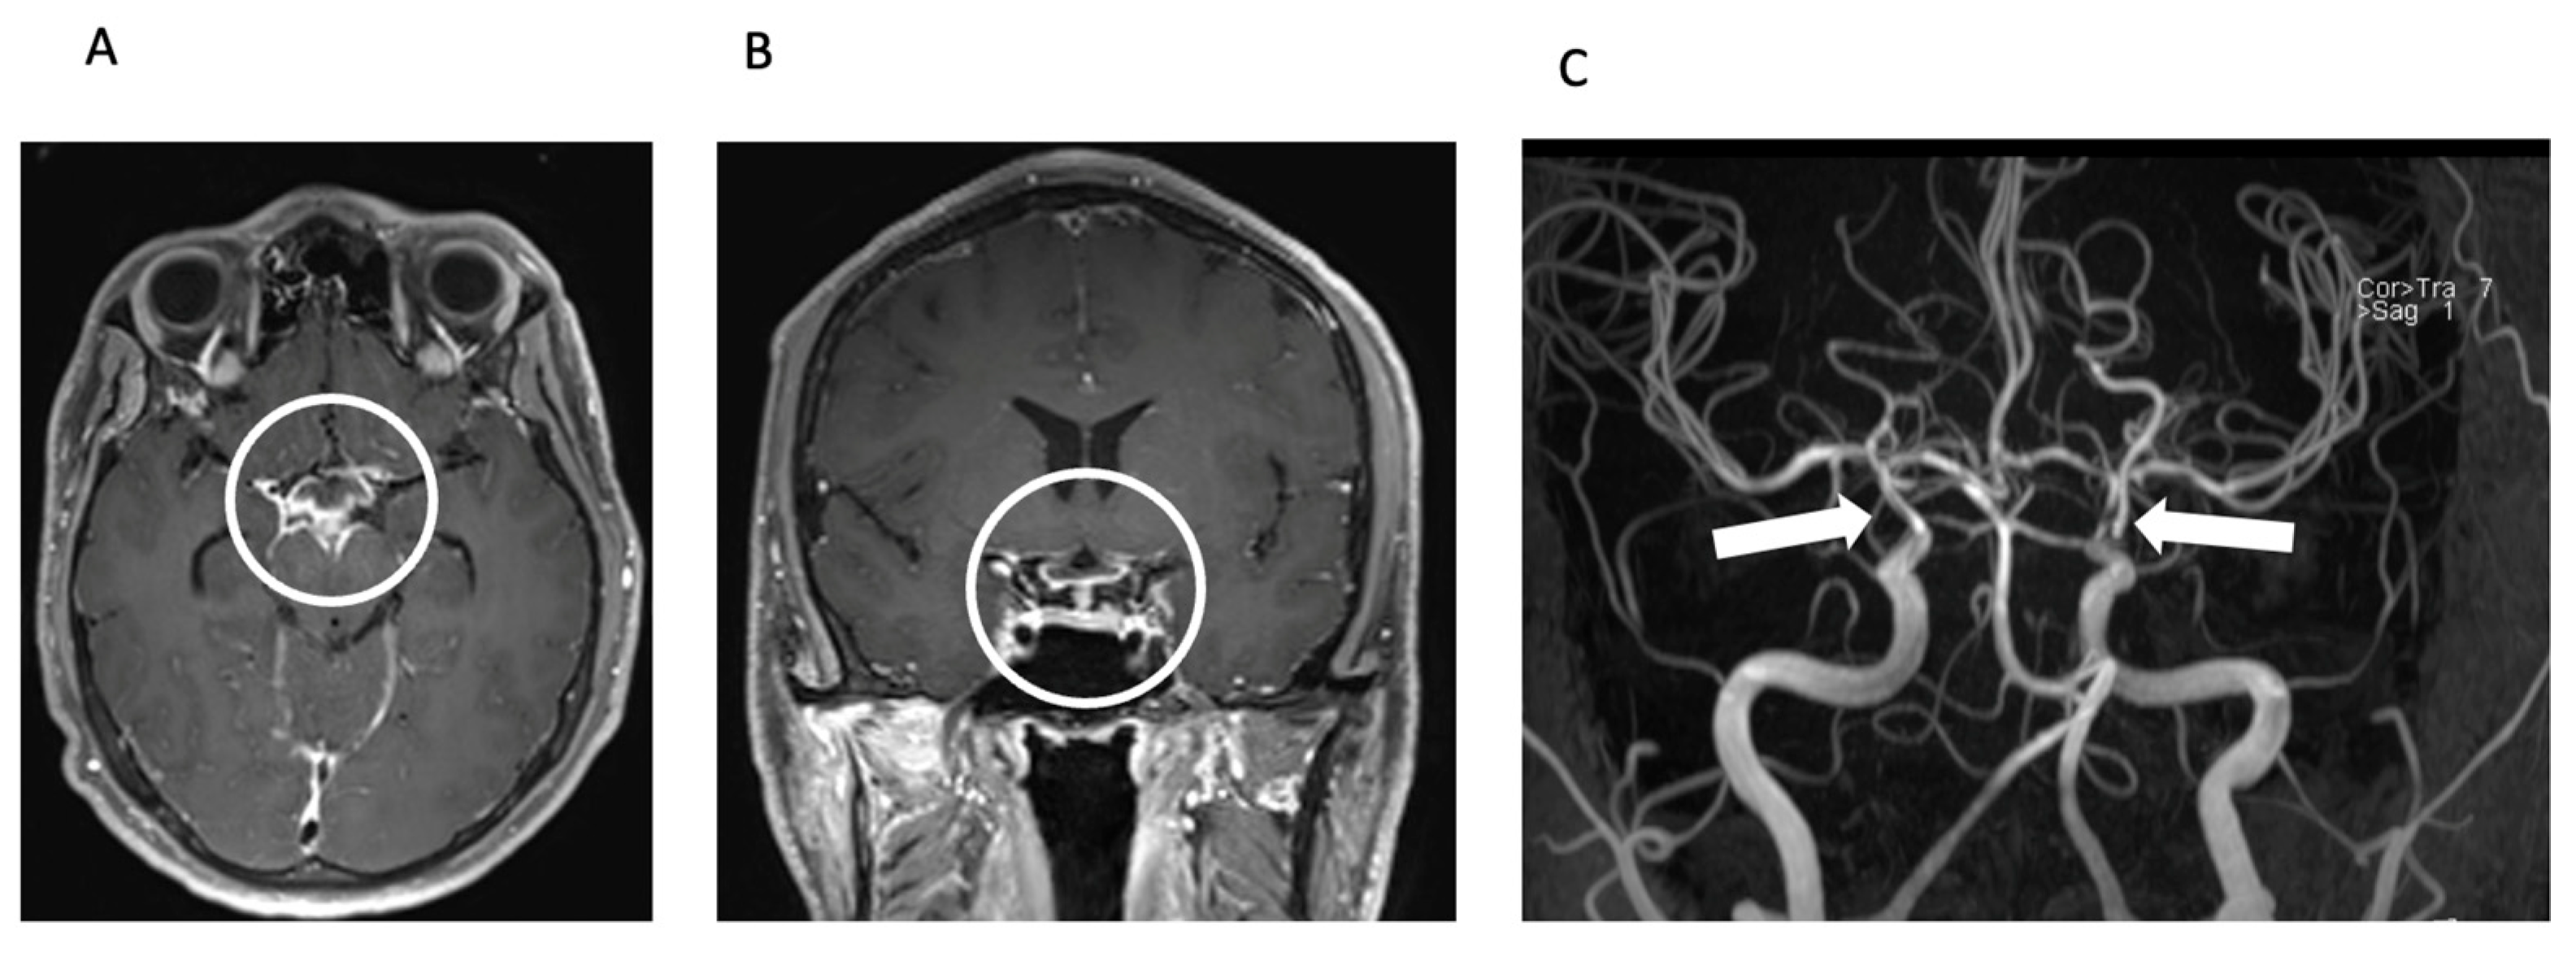

The radiologist’s observation of intraventricular contrast agent enhancement led to a suspicion of pyogenic meningitis with concomitant vasculitis (Figure 2).

Figure 2.

Meningitis and secondary CNS vasculitis on MRI. Axial (A) and coronal (B) reconstructions of contrast-enhanced T1 SPACE image showing basal contrast enhancement predominantly in the basal cisterns around the circulus of Willis (circle). TOF MR angiography (MIP, posteroanterior view—(C)) shows severe stenoses of the intradural proximal cerebral arteries, predominantly in the distal ICA including carotid T bilaterally (arrows).